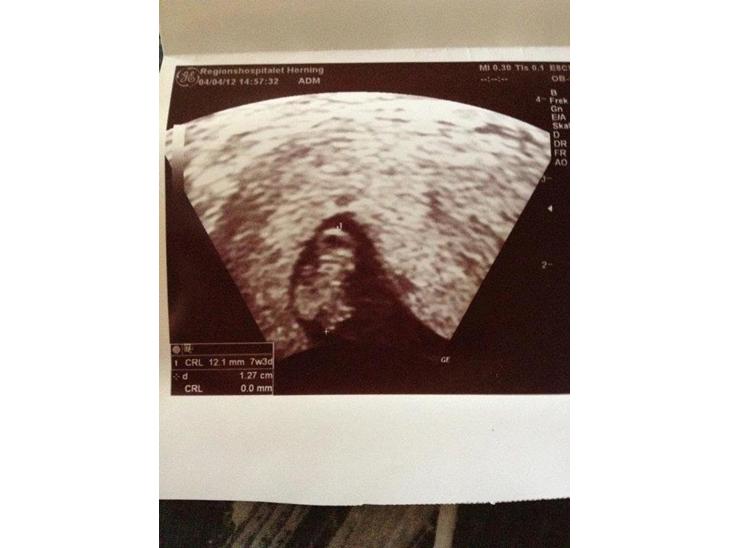

Lille piges scanningsbilleder